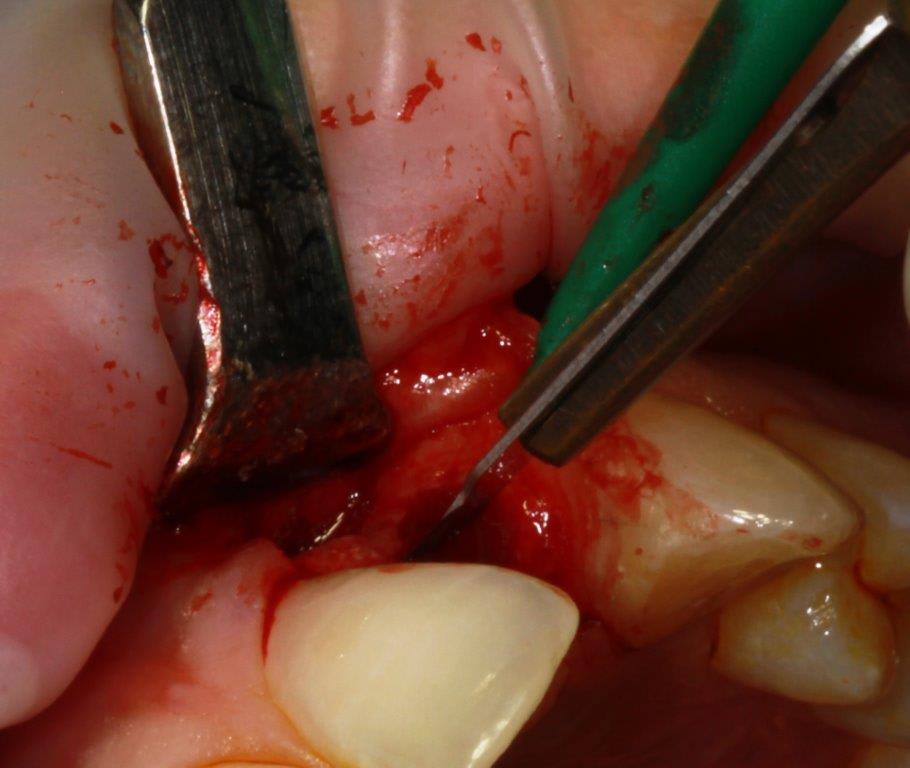

pour ceux que ça intéressent, une petite utilisation d'expansion de la paroi palatine, sur une avulsion d’incisive(racine fendue). toutes mes excuses pour la mauvaise qualité des photos.